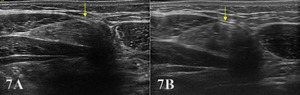

Typically, the transducer will be placed near the proximal portion of the RA perpendicular to the muscle fibers in the SAX. In this position, the transducer can be moved both proximally and distally and can examine the RA in the transverse plane. The cross-section of the RA will be seen as fibular hypoechoic muscle tissue. Additionally, the examiner should be able to easily discern the hyperechoic linea alba and rectus sheath.

For a view of the RA in the LAX, align the transducer parallel to the rectus fibers and then sweep medial and lateral to scan the entirety of the muscle belly and note the transition to the edge of the obliques. The rectus displays a linear fibrillar echo pattern of hypoechoic contractile tissue bounded by bright anterior and posterior sheaths. Tendinous intersections appear as thin echogenic bands that traverse the muscle at intervals. Above the umbilicus, the posterior sheath is typically present; below the arcuate line it is absent—a normal transition that should not be mistaken for a defect.

Pathologic Findings in Rectus Abdominus Injury

Intramuscular hypoechoic muscle tissue

Disruption of fibrillar pattern in partial tears and ruptures.

Associated hematoma.